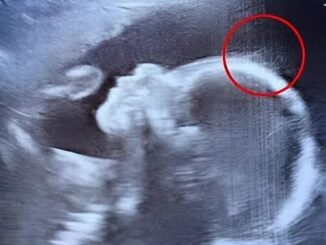

Doctors couldn’t believe what they saw during the ultrasound

When 29-year-old Emily Foster from Kent, England, walked into the hospital for her 20-week pregnancy scan, she expected the usual routine: a grainy image, a […]